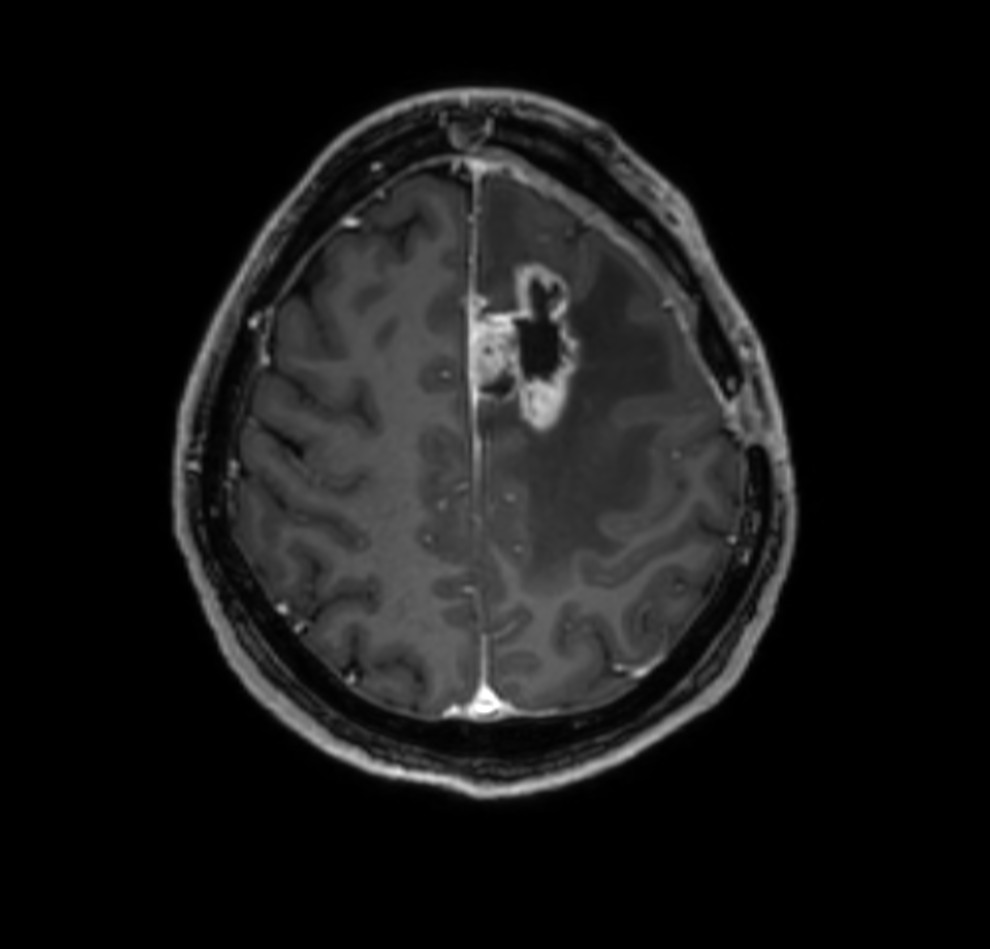

SmartSpeed Precise imaging for brain with glioblastoma